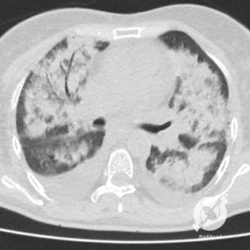

Opacidades em vidro fosco difusas com espessamento liso de septos e moderado derrame pleural bilateral.